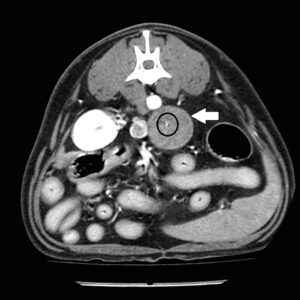

En estudios de TC sin contraste los feocromocitomas se observaron con valores más altos de Unidades Hounsfied (UH) con una atenuación media de 44,5 UH mientras que, en los adenocarcinomas, se observaron valores precontraste más bajos28,29. Esto puede deberse a que estos últimos se asocian con una mayor necrosis del parénquima o a que los feocromocitomas presentan con más frecuencia hemorragia intraparenquimatosa29. La angio-TC trifásica puede ayudar también a la diferenciación de las masas adrenales: se ha descrito que los feocromocitomas presentan una rápida captación de contraste en la fase arterial (imagen 6), mientras que los adenocarcinomas presentan un mayor realce en la fase venosa (imagen 7) y los adenomas un realce homogéneo en la misma fase32.

Imagen 7. Imágenes de TC en plano transversal en ventana de tejidos blandos sin contraste (A) y tras la administración de contraste en fase venosa (B) de un adenocarcinoma (flecha blanca) donde se observa un punteado hiperatenuante compatible con mineralizaciones (círculo). Tras la administración de contraste presenta el mayor realce en la fase venosa.